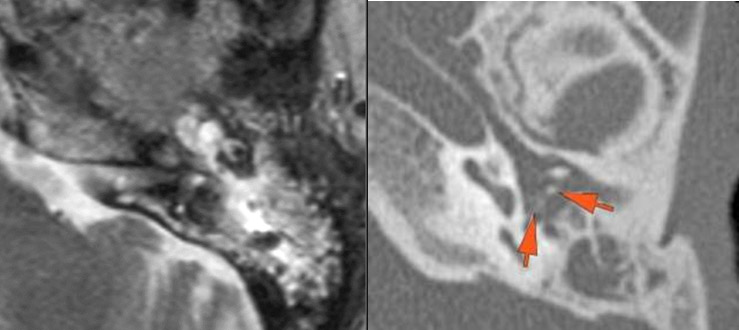

There is infiltration of the fat surrounding the nasolacrimal sac.

There is soft tissue infiltration or bone erosion along the nasolacrimal fossa or canal.